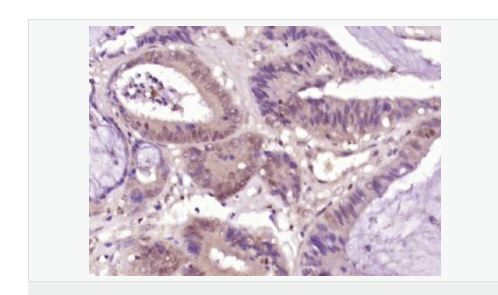

| 产品应用 | ELISA=1:5000-10000 IHC-P=1:100-500 IHC-F=1:100-500 IF=1:50-200 (石蜡切片需做抗原修复) not yet tested in other applications. optimal dilutions/concentrations should be determined by the end user. |

| 细胞定位 | 细胞核 |